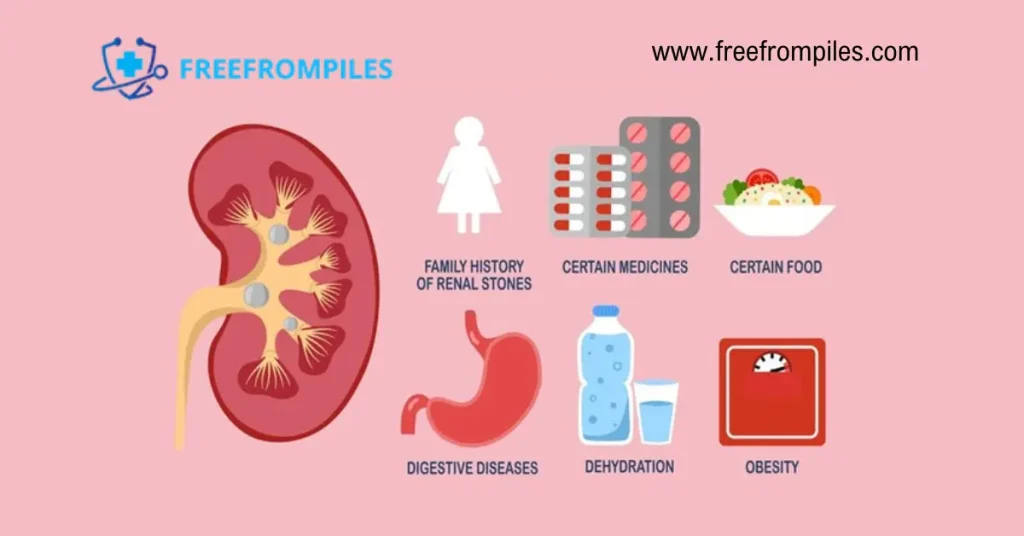

عوامل خطر سنگ کلیه: چه کسانی بیشتر در معرض خطر سنگ کلیه هستند؟

رنگ پوست: سفید پوستان بیشتر از سیاه پوستان – در میان آسیایی ھا شیوع متوسط

جنس : در مردان 2 تا 4 برابر بیشتر از زنان (به استثنای سنگ ھای استراویتی با شیوع بیشتر در زنان)

سن: بین 20 تا 40 سالگي(وجود سنگ کلیه زیر بیست سالگی غیر معمول می باشد و معمولا بین 20 تا 30 سالگی بیشترین میزان را دارد و تا سن 70 سالگی ممکن است ادامه داشته باشد ولی بعد از 70 سالگی شیوع سنگ کلیه کم می شود.)

سابقه فامیلي

سابقه خود فرد: فردي که قبلا داراي سنگ کلیه بوده است.

عفونت در لوله ھاي ادراري

کاھش مایعات بدن: به علت اسھال یا تعریق بیش از حد

بي نظمي و خوب عمل نکردن کلیه ھا

اختلال متابولیکي: مانند مشکلات در روده، غدد درون ریز و کلیه ھا

چاقی